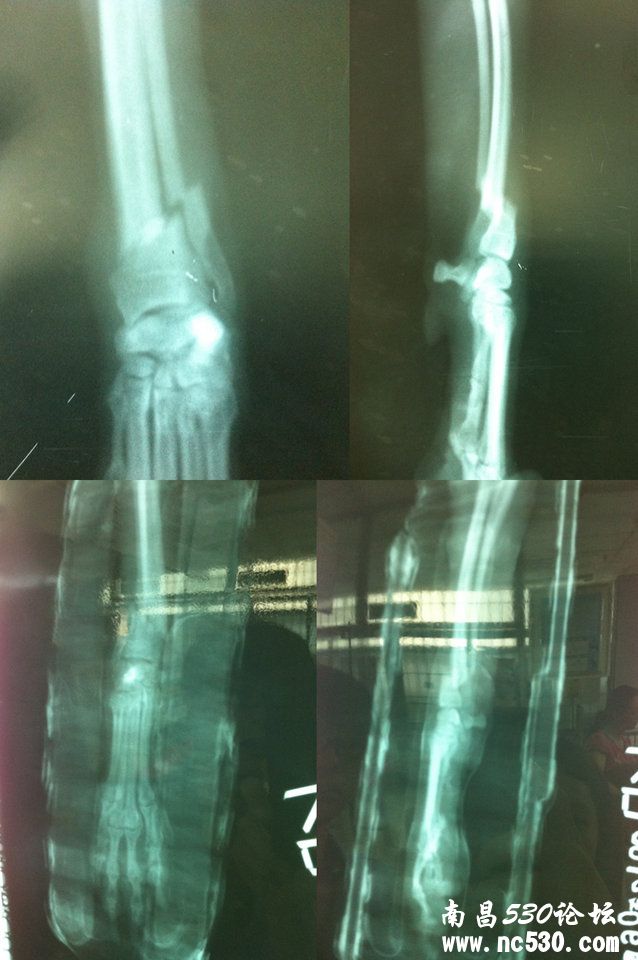

狗狗是5月16号摔倒骨折的~ 上面的片子是当时拍的片子~医生说骨折的部位不能做内固定~说没位置放钢钉,太靠脚掌。下面的片子是昨天6月5号去拍的片子,反光有些模糊~想请问医生昨天拍的为什么骨头还是歪的~尤其是侧面的那张,和原本的就没区别。这样是不是因为没有接好,会不会畸形愈合,有后遗症呢? 这个问题需要这样继续还是重新外固定 还是改为内固定呢? 还有就是骨折是需要吃什么好得快么?

我家童童(泰迪,5个半月)骨折刚拆了外固定8,9天了,拆了外固定的时候,拍的片子显示,都没有长好,只是有骨痂,但是骨痂没有对上。(我家外固定一个月)你的第二个片子看不清楚呀~~ 20天了,应该长骨痂了吧~~ 我家骨折吃了:钙片(医生给的) 卫仕液体钙,黄瓜籽粉,羊奶,喝过骨头汤,k9海藻粉。除了医生给的钙片和羊奶是每天吃,其他的都是隔几天喂一次,补钙太多了也不好~~ 我家童童现在的情况是:4条腿走路,小跑(用伤腿挠痒痒),但是快跑还是3条腿。后期的康复很重要。。。给我做外固定的那个医院让我内固定,我当下没有内固定,然后又跑了5家宠物医院,有问了一个开狗舍30年的人,都建议我保守治疗,只要狗狗可以4条腿走,就没有问题。你如果还有什么问题可以站内我,因为我很能理解你的心情,一个多月前我家狗狗骨折的时候,我真是痛不欲生呀~~